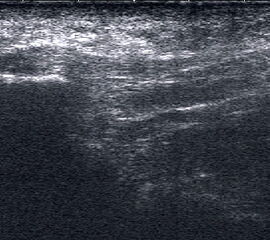

Dorsaler TS hinter dem Innenknöchel.

Abbildung 46

Lagerung: Rückenlage, Außendrehung des Beines.

Schnittführung: TS und LS hinter dem Innenknöchel beginnen und bis zum Os cuneiforme mediale fortführen.

Referenzstrukturen: Innenknöchel, Talus, Os naviculare, Os cuneiforme mediale, Sehnen der Mm tibialis posterior, flexor hallucis longus, flexor digitorum.

Befunde: Häufig betreffen die Pathologen die Tibialis-posterior-Sehne, die als erste Sehne hinter dem Innenknöchel zur Darstellung kommt. Halo-Phänomen und echoarme Verdickung bei akuter Tendinopathie, zunehmend inhomogen und echogen mit Kaliberschwankungen bis hin zu Teilrupturen bei Chronifizierung 5. Für die Erkennung von Teilrupturen sind TS in verschiedener Höhe besonders wichtig. Bei komplettem Riss mit Retraktion im LS Bild wie Spargelspitze mit umgebender Flüssigkeit oder Hämatom. Ein Os tibiale externum erscheint als echoreiche Struktur im Verlauf der Tibialis posterior Sehne mit dorsaler Schallauslöschung. Ein Os naviculare cornutum imponiert als starke Prominenz im Ansatzbereich der Tibialis posterior Sehne.